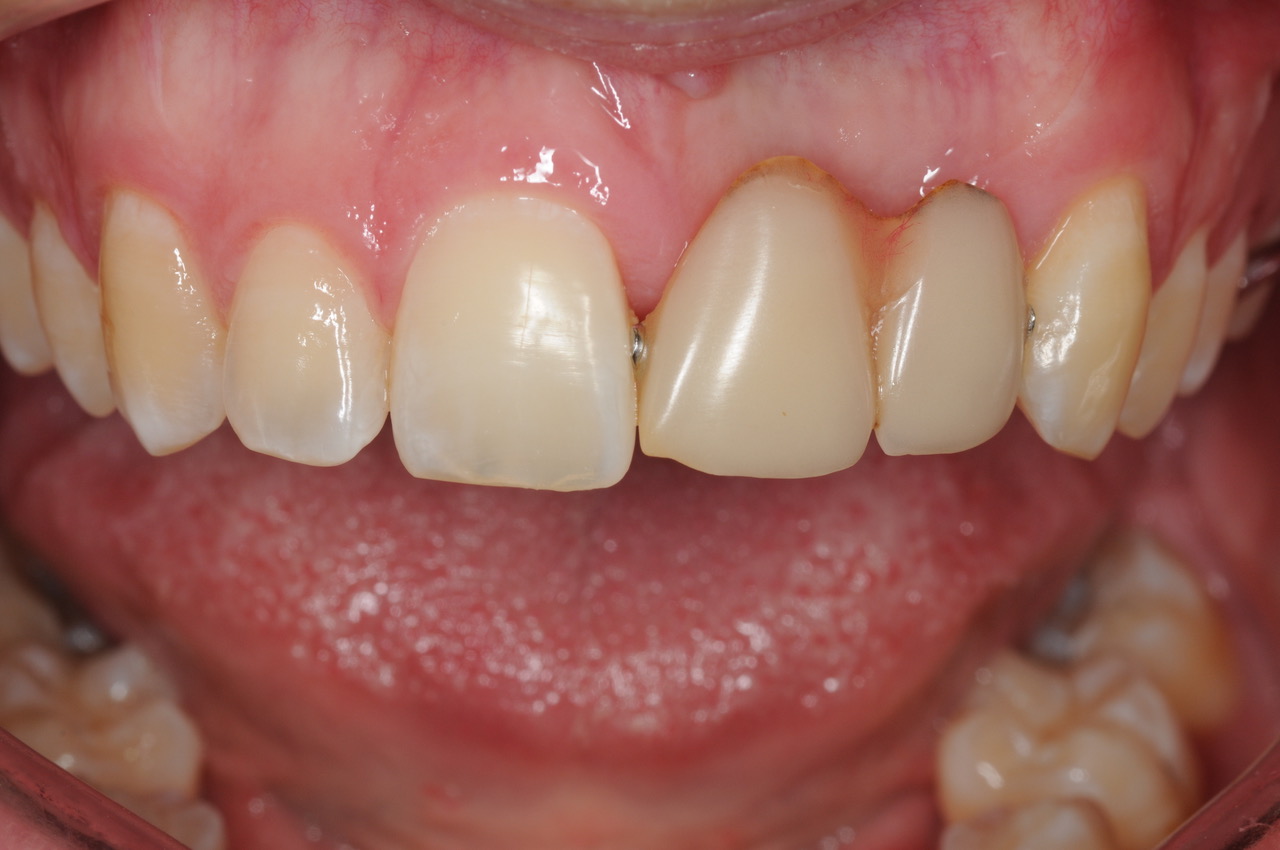

This young man was missing his left central and lateral incisors. He wore a partial denture to replace these two teeth

He did not like the partial denture as it was bulky in his mouth, often came loose while he was eating, and it had stained and worn which made him uncomfortable about his smile.

As the teeth had been missing for many years, there was quite a bone and soft tissue defect. Some grafting procedures were required for this case.

The implant was placed, healing was allowed to progress for nearly 6 months (due to the grafting stages), and the young man continued to wear his partial denture during this time.

One restorative abutment was placed on the implant and then a 2-tooth cantilever bridge was placed on the abutment. The final result appears to be two teeth, but in fact, they are joined together as a bridge, and they are only supported by the one implant, which is in the central incisor position. This design is very functional and also easy for the patient to clean.